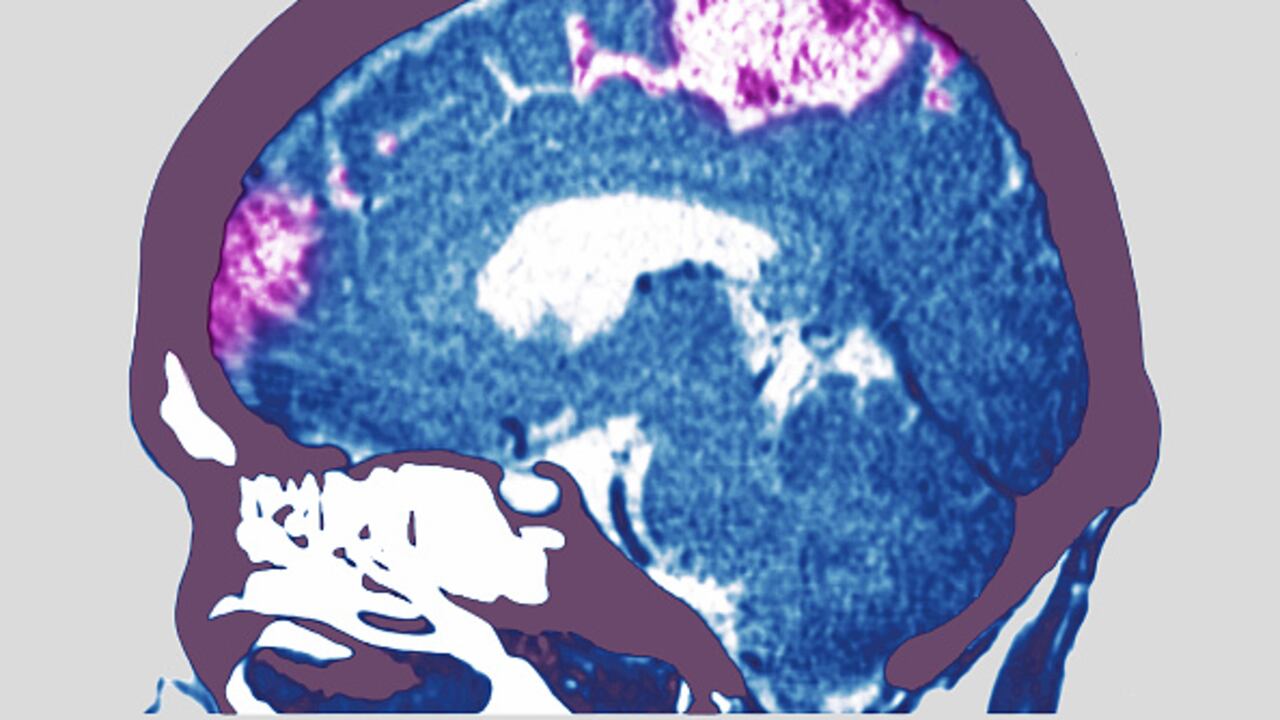

Un derrame cerebral o accidente cerebrovascular se presenta cuando se interrumpe o se reduce el suministro de sangre a una parte del cerebro, lo que impide que los tejidos reciban oxígeno y nutrientes, por lo que las células pueden morir, causando daño permanente, precisa la Biblioteca Nacional de Medicina de Estados Unidos.